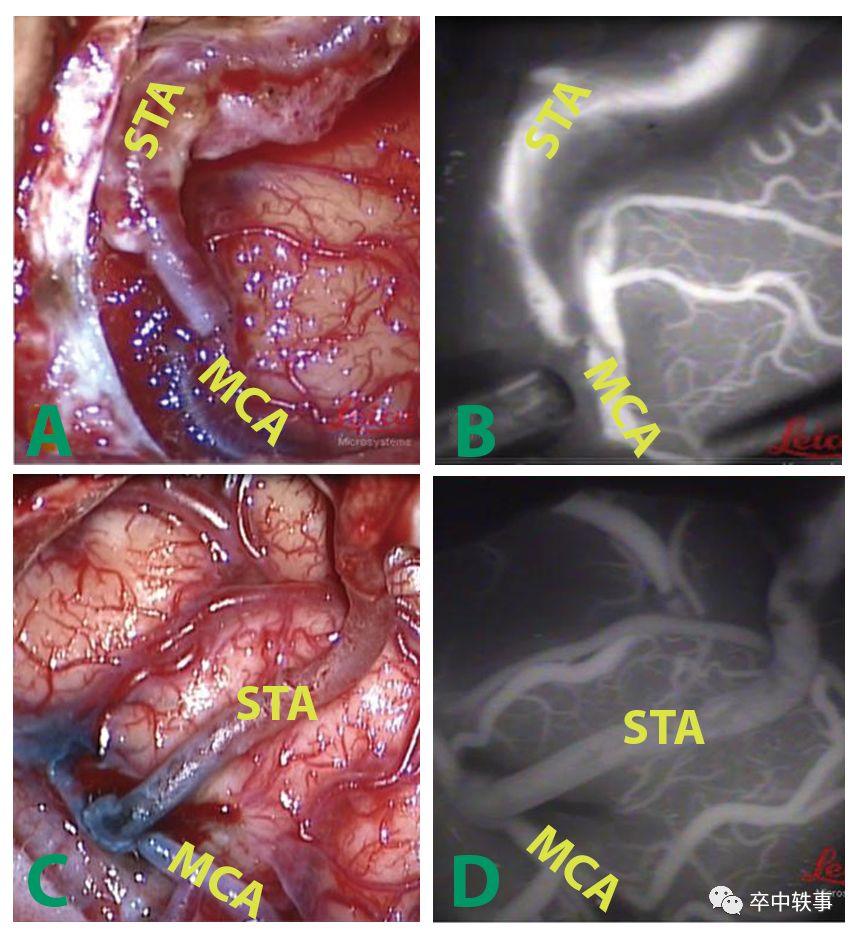

第一例用颞浅动脉 - Superficial Temporal Artery (STA) - 与大脑中动脉 - Middle Cerebral Artery (MCA) - 的搭桥手术是在1967年由 Mahmut Gazi Yasargil(1925-)创意并实施的。

可以说逢山开路,建立新的脑血供的设想早就有了,但是一直无人尝试。有创新意识的 Yaşargil 在1967年做了历史上第一例 STA-MCA 搭桥手术,从颅外开启了第五条入颅大通道。

使用股动脉的失败使 Yaşargil 想到用离大脑中动脉很近的颞浅动脉作为供体,不需要取下,可以直接拐弯,穿越颅骨,与大脑中动脉相连。在1966年底他做了30只狗的 STA-MCA 搭桥实验,取得成功。

Yaşargil 回到苏黎世大学,在1967年10月30日为一个大脑中动脉完全阻塞的马凡氏综合征病人做了第一例 STA-MCA 搭桥手术。据说 Donaghy (下图右) 在1967年10月31日也做了一例搭桥手术,比 Yaşargil 晚了一天。